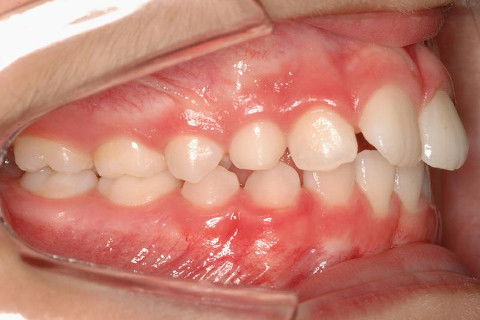

LATERAL DIR. INICIAL

PACIENTE CLASSE II.

ATRESIA DE MAXILA.

SOBREMORDIDA.